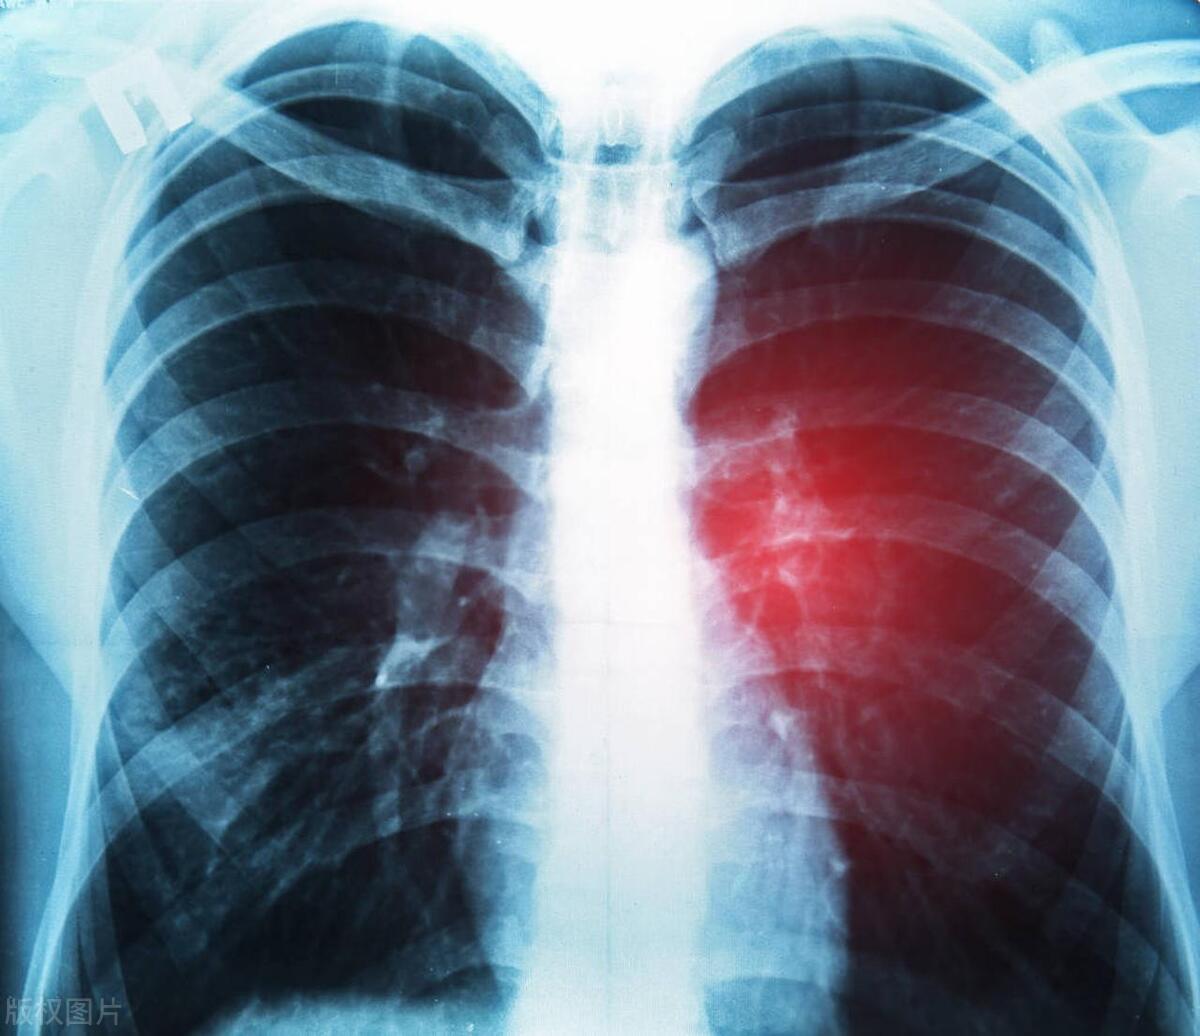

最近,李女士感覺自己的身體出現了一些異常症狀,比如咳嗽、咳痰、胸痛等。李女士誤以爲自己只是感冒了,於是隨意服用了一些感冒藥,希望症狀能夠有所緩解。然而,喫了藥之後,她的症狀並未得到緩解,反而呈現出愈發嚴重的趨勢,這讓她開始感到焦慮和不安。她只好去醫院檢查。

經過一系列嚴謹而細緻的檢查,醫生遺憾地發現李女士的身體狀況並不樂觀,她被確診患上了肺癌,這一消息無疑給她和她的家人帶來了沉重的打擊。醫生告訴她,肺癌的發生與她的生活方式和飲食習慣有很大關係。李女士長期吸菸、飲酒且缺乏鍛鍊,這些因素導致她免疫力下降,容易感染病毒和細菌,無形中增加了患肺癌的風險。

得知自己患上肺癌後,李女士深感懊悔,她深刻反思了自己的不良生活習慣,並意識到這些習慣給自己帶來的嚴重後果。李女士痛定思痛,決定徹底改變自己的生活方式和飲食習慣,同時積極配合醫生的治療方案,爭取早日康復。經過一段時間的治療,李女士的病情得到了控制,身體狀況也有所改善。